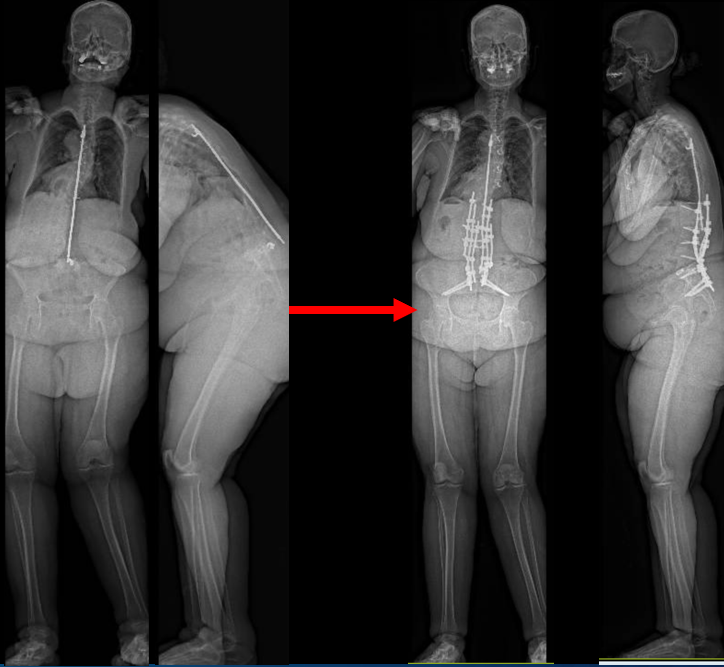

From robotics and AI-driven surgical planning to virtual modeling and custom implants, I’ve embraced a combination of tools that allow me to create tailored surgical plans for my patients—particularly those with scoliosis and spinal deformities.

What sets my approach apart is the seamless integration of these advanced technologies to ensure unparalleled accuracy and better outcomes for each patient.